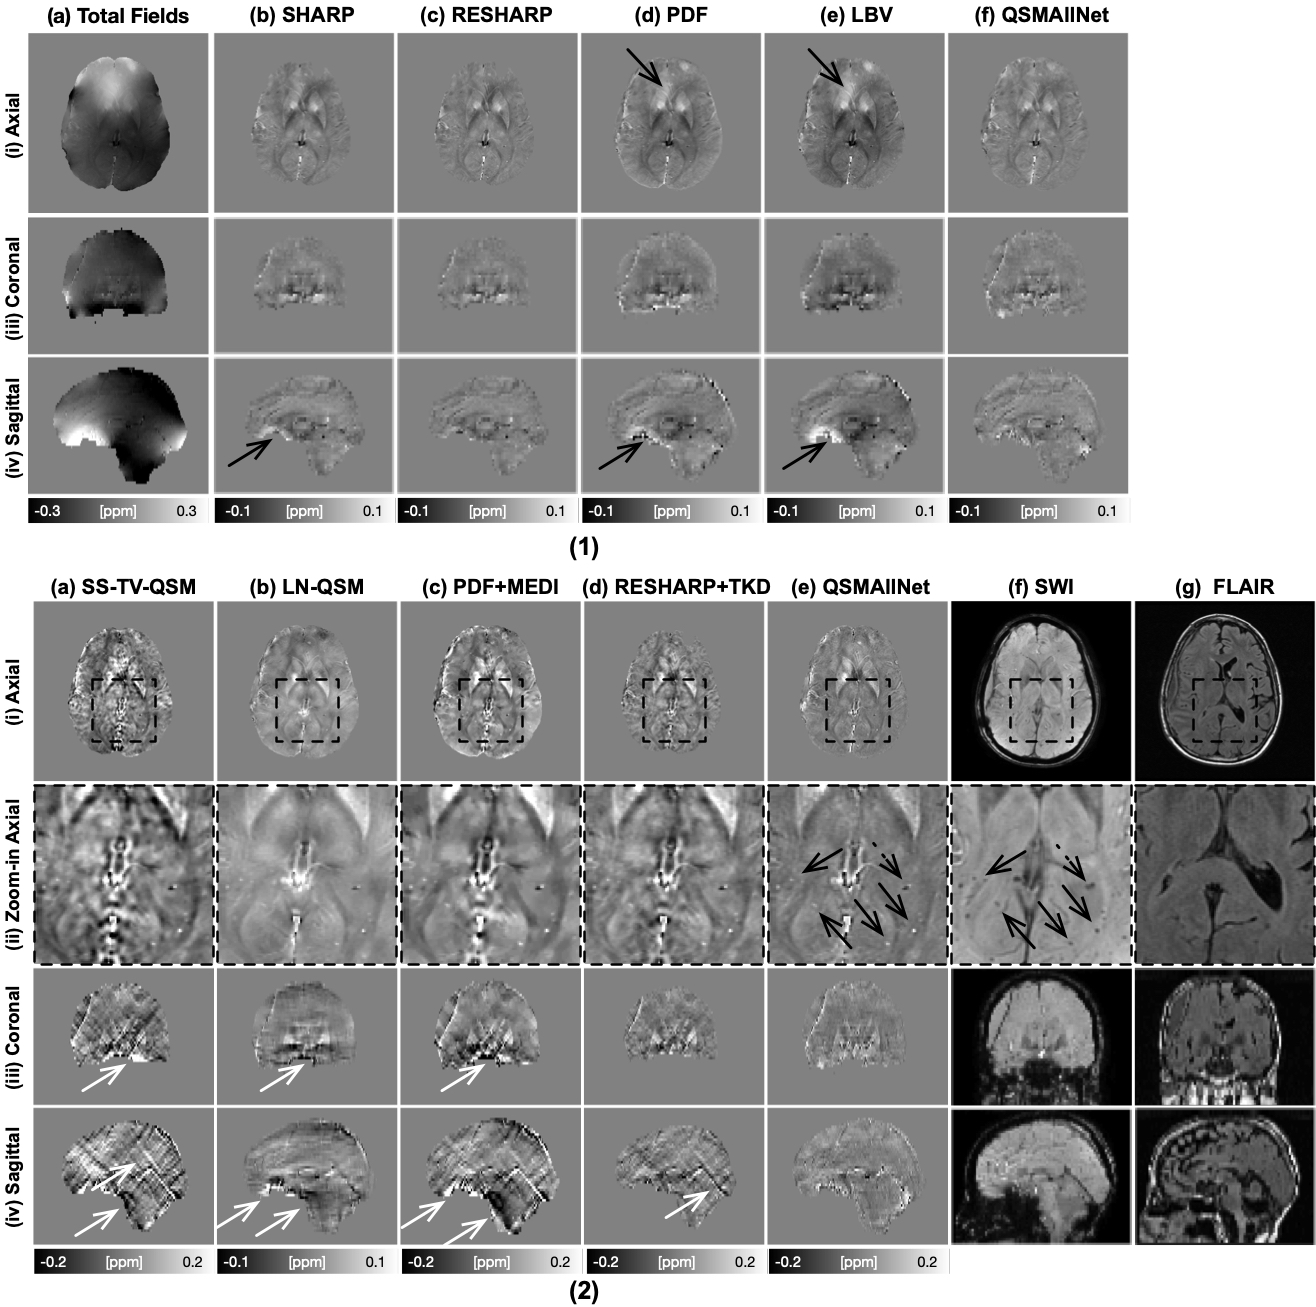

In Fig. 7, background removal results and susceptibility images of a 37-year-old subject with meningioma and multiple sclerosis is illustrated. Residual background field is visible in SHARP, RESHARP, PDF, and LBV results (1, a-d, i-iv). PDF and LBV results show obvious shading artifacts (1, c-d, i-iv). From the QSM images, SS-TV-QSM, PDF+MEDI, and RESHARP+TKD suffers severe image blurring and streaking artifacts, as shown (2, a, c, d, i-iv). LN-QSM shows strong shading artifacts, as shown (2, b, i-iv). With comparison to other methods, QSMAllNet results (2, e, i-iv) showed improved image sharpness, clear tissue structures, and no image artifacts.

Figure 7: Total fields and QSM background removal results (1), susceptibility images, SWI images and FLAIR images (2) on a xx-year-old subject with xxx. In (1), residual background fields are clearly visible in SHARP, RESHARP, PDF and LBV (b-d) results in axial and saggital views. SHARP and RESHARP results (b-c) have brain erosion. LBV and PDF have shading artifacts in the tissue fields. QSMAllNet results show better background field removal. From the susceptibility maps (2), SS-TV-QSM, LN-QSM, PDF+MEDI, and RESHARP+TKD have susceptibility large estimation errors, especially streaking artifacts and shading artifacts ( white arrows). Based on visual comparison, QSMAllNet can produce improved local field and susceptibility estimation.